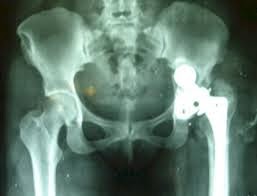

El artista conceptual noruego Alexander Selvik Wengshoel, tuvo una operación de cadera y le pidió a los médicos sus huesos para un proyecto de arte.

El artista, que estuvo toda su vida condenado a una silla de ruedas y tuvo que soportar varias operaciones sin éxito dijo que comer su propia carne fue una manera de ayudarle a depurar el dolor.

“El hueso de la cadera ha sido un problema para mí durante más de 20 años. Fue tan duro para mi vida que cuando lo saqué, se convirtió en algo más, en algo romántico,” concluyó.